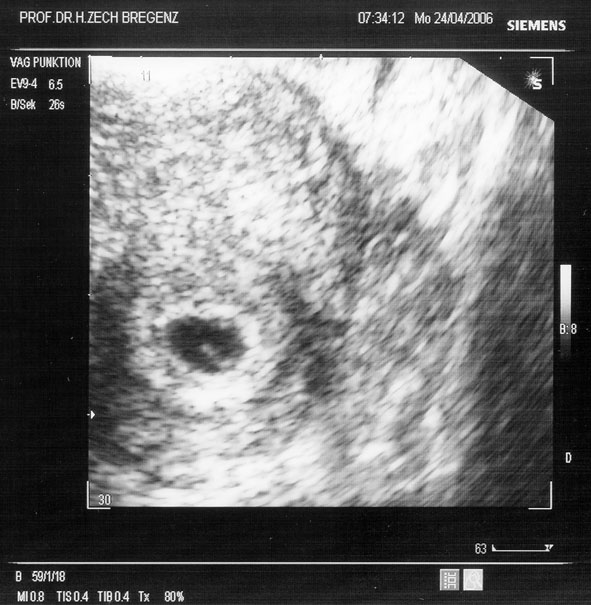

gratulation zu den tollen fotos *neid * jetzt seid ihr wirklich schwarz auf weiss schwanger, wie toll

Schöne Fotos habt ihr da! *selberneidischbin*